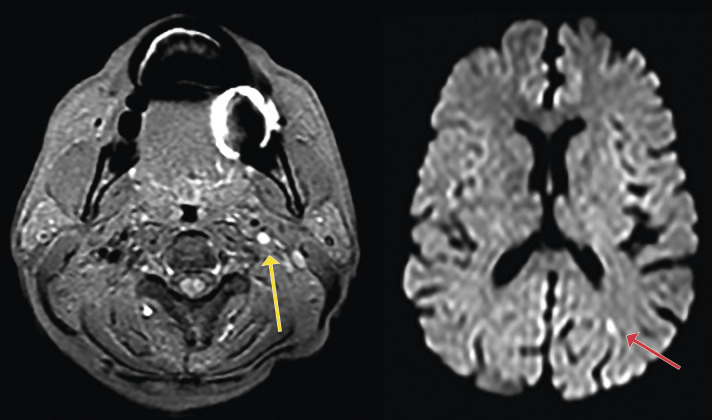

Une prise en charge en urgence des AIT de moins de 48 h diminue de près de 80 % le risque de récidive d’AVC. La conduite doit être identique lors d’un TVT supposé d’origine ischémique. Cela implique de réaliser dans l’idéal une IRM cérébrale + ARM des TSA (fig. 2) dépistant un patient à haut risque de récidive (angioscanner si contre-indication ou échodoppler des troncs supra-aortique [TSA] et transcrânien [TC]) et de débuter en urgence un traitement adéquat : endartériectomie pour une sténose carotidienne symptomatique ≥ 70 % (bénéfice prouvé par l’étude NASCET, même s’il est moindre que pour les AIT), anticoagulant pour une FA, antiagrégant (simple par aspirine ou double avec dose de charge pour les AIT à haut risque ou AIC mineur) et statine en cas d’atteinte athéromateuse.

Il est possible de stratifier le risque d’AVC après un AIT selon le score ABCD2 et l’IRM cérébrale couplée à une angio-IRM (ARM) des vaisseaux du cou et intracrânienne. De même, lors d’ischémies rétiennes constituées ou transitoires, l’IRM cérébrale est positive en diffusion dans près de 25 % des cas ; il s’agit de lésions ischémiques punctiformes, associées à une cause à haut risque de récidive (sténose serrée, dissection carotidienne ou cardiopathie emboligène). Cet examen serait positif dans 11 % des CMT (fig. 1). Dans le service SOS AIT de Bichat, 34,4 % des patients avaient des TVT dont 50 % isolés. L’IRM était positive dans 5,9 % des cas (11,8 % si hémianopsie latérale homonyme ; cette dernière était plus souvent associée à une FA : × 2,5 par rapport aux AIT sans TVT).